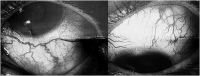

The aim of the case series is to highlight the surgical challenges experienced like failed intervention, choroidal effusion, a postoperative cystoid macular oedema, and describe treatment options for Radius-Maumenee syndrome. Authors reported on 3 bilateral cases of Radius-Maumenee syndrome which underwent medical treatment, trabeculectomy with Mitomycin C, implantation with XEN45, Ahmed glaucoma valve, Baerveldt glaucoma implant, and cyclophotocoagulation.